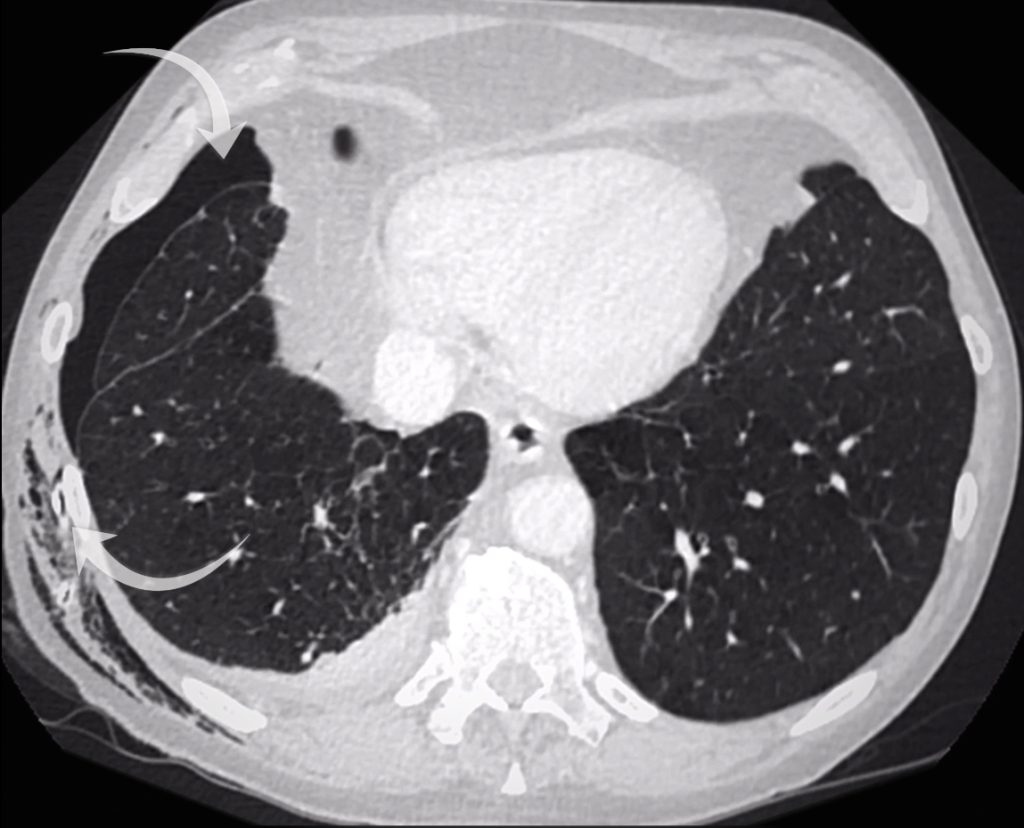

A chest drain was inserted, but the patient’s breathlessness didn’t improve, a red flag suggesting the drain might not be in the right place. Now have a look at the CT scan in this case.

• The chest drain is in the chest wall, not in the pleural space, explaining why the pneumothorax persists.

• There is severe emphysema and a small right pleural effusion.

• The two lung opacities are confirmed:

• One in the apical right lower lobe (corresponding to the opacity behind the hilum).

• One in the right upper lobe.

The chest drain is out side of the pleura (bottom arrow) and the pneumothorax persists (top arrow). There is a small right pleural effusion.